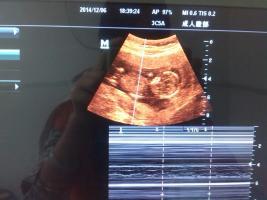

谁能帮忙看B超图片,以下是孕40天与孕13周照的B超图,现在是二胎压力大啊,请帮忙看看吧